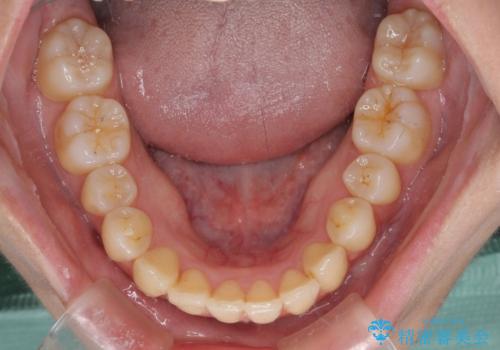

- 上の前歯、および下の歯列全体のでこぼこを気にして来院された患者様です。

インビザラインを用い、IPR(歯と歯の間を削る)と歯列全体を後方に移動させることで、歯並びを整えていくこととしました。

歯列全体を後方に移動させるため、下顎の親知らず2本を抜歯することとしました。